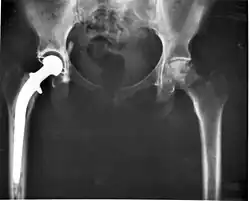

Nos últimos 45 anos, a técnica mais bem-sucedida e comum de artroplastia é a substituição cirúrgica de articulações necróticas ou fraturadas por uma prótese. Por exemplo, uma articulação do quadril afetada por osteoartrite avançada pode ser totalmente substituída por uma prótese de quadril. Isto significa substituir tanto o acetábulo (no quadril) quanto a cabeça e pescoço do fêmur. A finalidade deste procedimento é aliviar a dor, restaurar a amplitude de movimento e melhorar a capacidade funcional, melhorando inclusive a força muscular.